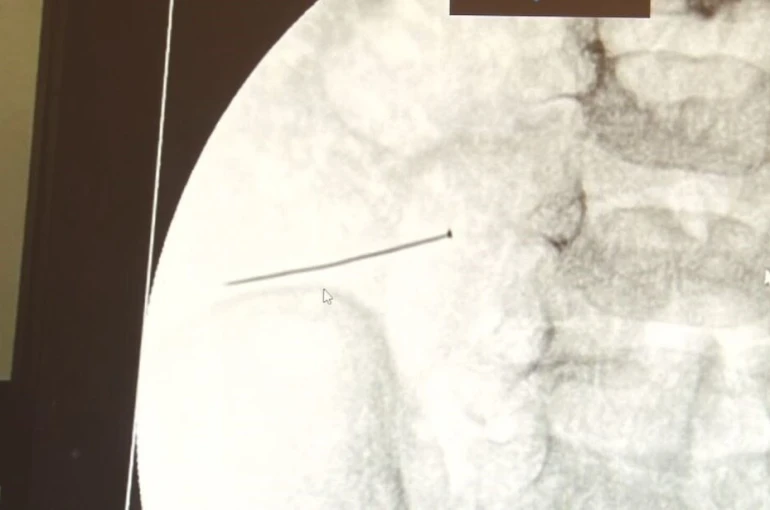

Öte yandan, yaklaşık 3 santimlik toplu iğne filme yansıyan görüntüsüyle gözler önüne serildi.

İstanbul’da 2 yaşındaki çocuk iddiaya göre toplu iğne yuttu sonrasında adeta karın ağrısıyla yerinde duramaz hale geldi. Babaanne, küçük çocuğun şikayetleri üzerine Şehit Prof. Dr. İlhan Varank Sancaktepe Eğitim ve Araştırma Hastanesi’ne götürdü. Burada yapılan tetkiklerde 2 yaşındaki çocuğun ince bağırsağında yaklaşık 3 santimlik toplu iğne olduğu ve bağırsağı deldiği belirlendi. Görüntülemeler sonrası 30 Ekim akşamı Çocuk Cerrahisi Kliniği Eğitim ve İdari Sorumlusu Doç. Dr. Sefa Sağ ve ekibi hemen ameliyata girdi. Başarılı operasyonla iğne olduğu noktadan alınırken aile de rahat bir nefes aldı. Doç. Dr. Sağ ise taburcu edilen hastasının durumuna ilişkin bilgi verirken yabancı cisim yutmalarına karşı ailelere önemli uyarılarda bulundu.

Çocuklarda yabancı cisim yutulmasına yönelik konuşan ve hastasına ilişkin bilgi veren Doç. Dr. Sefa Sağ, "Soluk borusuna kaçması durumunda çocuğun Allah göstermesin ölümüyle veya ömür boyunca yatağa bağımlı kalmasıyla neticelenebilecek sonuçlar doğurabiliyor. Yutulması durumunda da gastrointestinal sistemin herhangi bir yerine takılmadığı müddetçe ekseriyâ yabancı cisimlerin dışarıya çıkmasını bekliyoruz. Yabancı cisim yutulmasını 2 grupta inceleyebiliriz. Sıvı ve katı cisimler olarak sıvı; evde kullanılan kimyasal temizlik malzemelerinin yutulması çok ciddi problemler oluşturabilmekte. Ağızda, yemek borusunda ve midede yanıklar meydana getirebilmekte. Uzun dönemde çocukların hayat kalitesini oldukça etkileyen sonuçlar doğurabilmekte. Katı cisimlerden de ekseriyâ kendiliğinden çıkmasını bekleriz ancak böyle delici, kesici aletlerin yutulmasında ise herhangi bir bağırsağın veya gastrointestinal sistemin bir parçasında delinmeler meydana getirebiliyor. Bu çocuğumuzda da aynen böyle bir hadise meydana gelmişti. Sanırım 1 gün önce ailenin yuttuğunu tahmin ettiği bir yabancı cisim; toplu iğne. Ertesi gün bağırsakta delinmeyle sonuçlanmış ve çocukta da ciddi semptomlar meydana getirmişti. Bu şekilde hasta bize başvurdu. Tetkikler sonucunda yabancı cismi tespit ettik, semptomları ve bulgularına göre de çocuğu ameliyata aldık. Yaklaşık 3 santim boyunda bir toplu iğnenin ince bağırsağı deldiğini, ince bağırsaktaki içeriğin de karın içerisine dolduğunu gördük. Ameliyatı başarılı bir şekilde tamamladık, yaklaşık 1 saat süren bir ameliyattı" dedi.